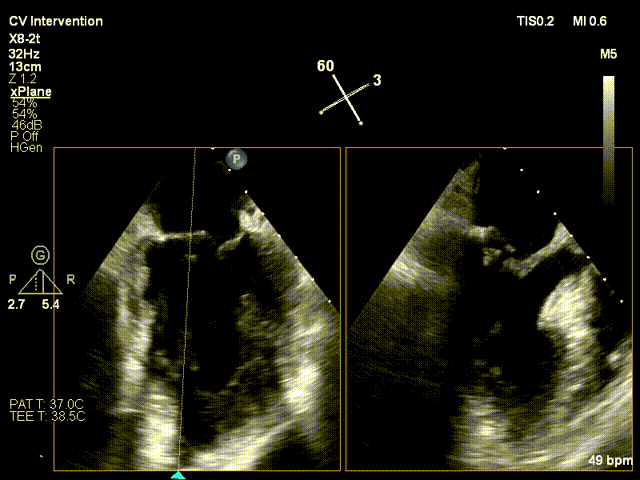

行TEE示:二尖瓣后叶脱垂合并重度反流(DMR4+)。左室后内乳头肌断裂,二尖瓣后叶腱索断裂。二尖瓣前叶长度17.6mm, 后叶有效长度6.1mm,二尖瓣后叶P2区脱垂,MVA 4.63cm²;PISA定量 EROA=0.72cm²。

心超参数: